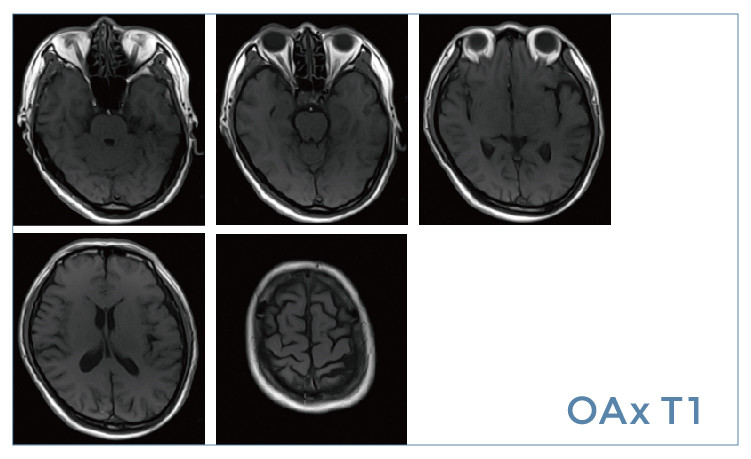

【朗润影像档案】磁共振影像病例分享(编号20190524)